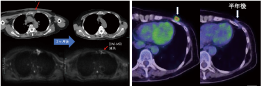

当院のBNCT症例

写真内の電子捕獲は一貫しています。CT では捉えられない播種の例が再発病変の周囲で見つかりました。 この種の再発病変は通常乳がんですが、病変の範囲を特定するのは容易ではなく、放射線治療、陽子線、重粒子線は適していません。

BNCT は巨大な腫瘍を治療できます。ただし、他の放射線療法と同様、画像検査で腫瘍が縮小し始めるのは治療後 2 か月目以降です。